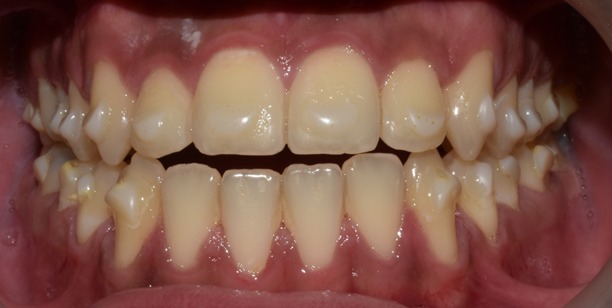

Before & After Results

At Aline Dent, we take pride in delivering visible and lasting improvements in our patients’ smiles. Our before-and-after results highlight the effectiveness of modern dental treatments combined with personalized care. This gallery showcases real dental cases treated at our clinic, giving you a clear idea of how different dental concerns can be corrected with the right treatment approach.

From minor corrections to complete smile enhancements, these teeth transformation results demonstrate how professional dental care can improve both oral health and appearance. Our experienced dental team carefully evaluates each patient’s needs and creates customized treatment plans to achieve natural, healthy, and confident smiles.

In this gallery, you will find a variety of smile makeover cases, including treatments for crooked teeth, gaps, discoloration, damaged teeth, and other common dental concerns.